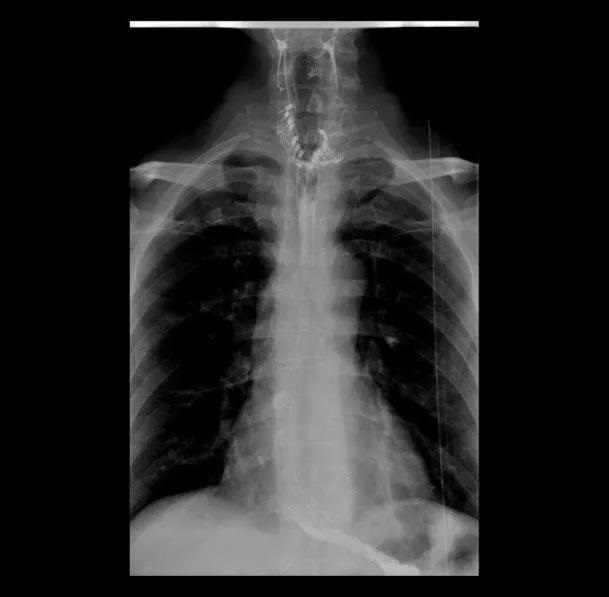

▲术后上消化道造影可见食管上段囊袋消失